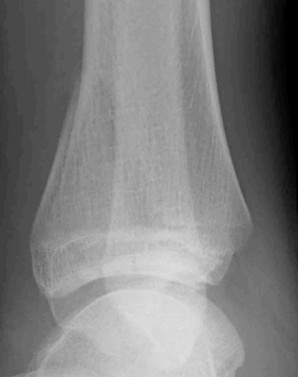

A 13-year-old girl sustains an ankle injury during a soccer match. Radiographs reveal an isolated Salter-Harris III fracture of the anterolateral distal tibial epiphysis (Tillaux fracture). Which of the following describes the anatomical sequence of distal tibial physeal closure that predisposes adolescents to this specific fracture pattern?

A 13-year-old female sustains a fracture of the anterolateral aspect of her distal tibial epiphysis after an external rotation injury. This fracture pattern (Tillaux fracture) occurs specifically due to the asymmetrical closure of the distal tibial physis. In what sequence does the normal distal tibial physis close?